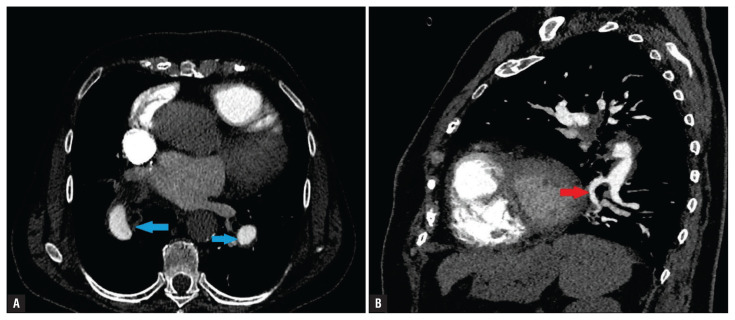

Abstract Image